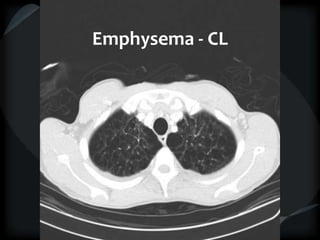

Emphysema - CL

Hyperlucency

Centrilobular emphysema

Paraseptal emphysema

Panacinar emphysema

CL + PSemphysema